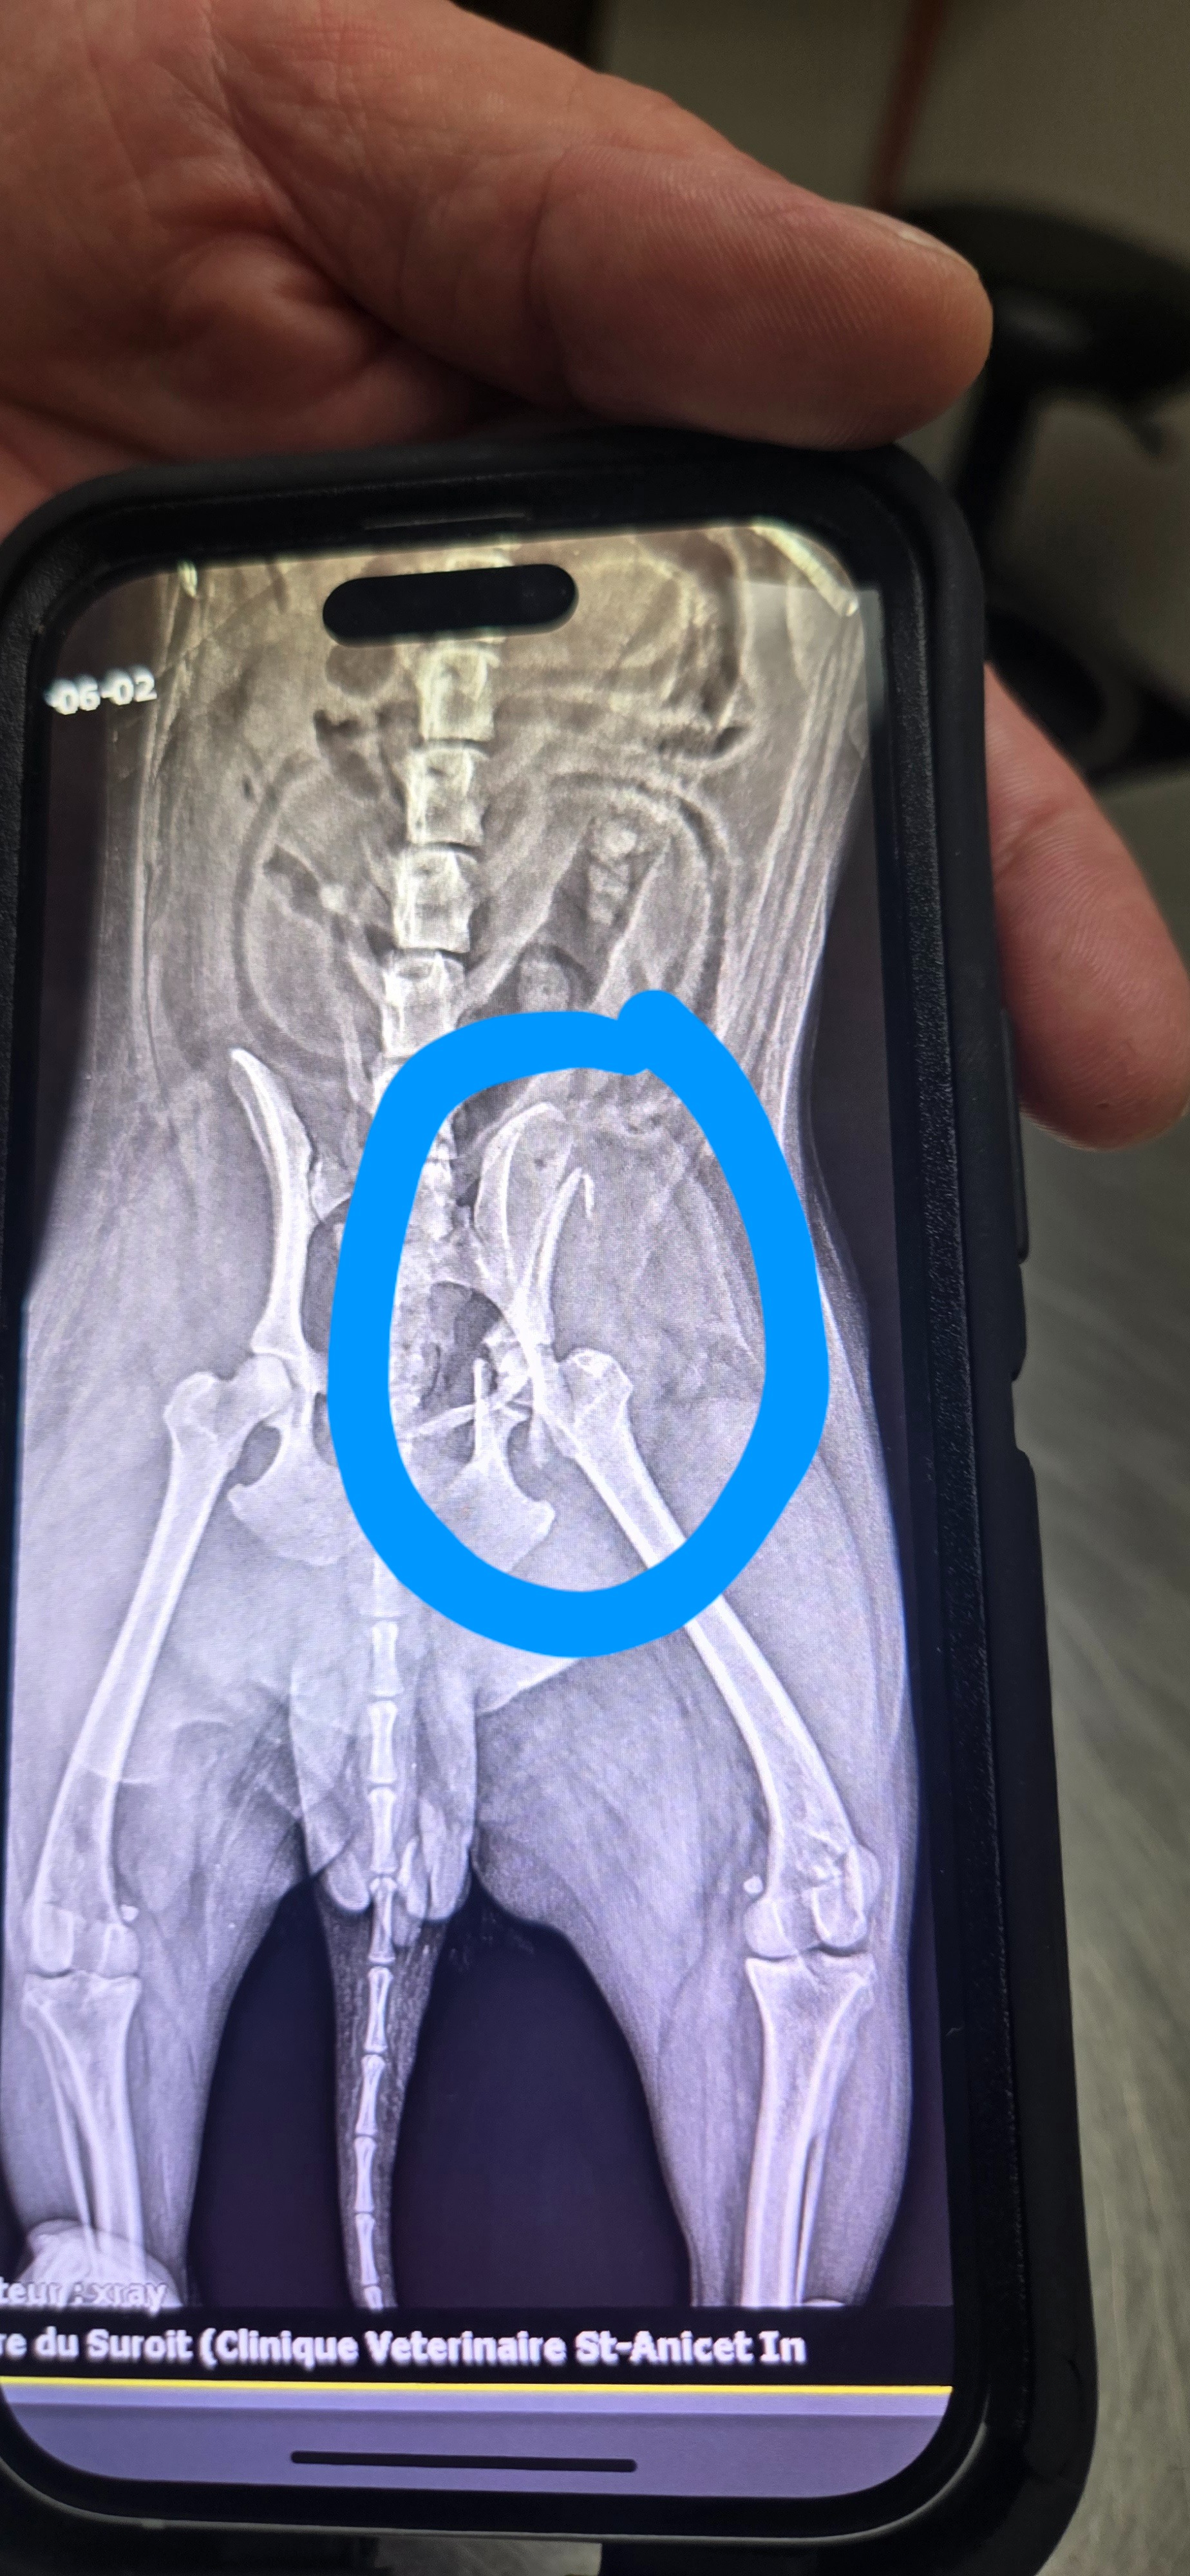

Bonjour, je m’appelle Alexandre et aujourd’hui notre chien, Gaïa, s’est fait frapper. Un vrai amour qui en donne plein à mes trois enfants, ma conjointe, mon chat Budy et moi même. Elle ne quitte jamais le terrain, mais aujourd’hui fût une autre histoire. Nous étions sur le terrain, de l’autre côté de la clôture, pour quelques minutes. Son meilleur ami Budy est venu nous voir. Gaïa et Budy ont l’habitude de jouer ensemble et de se courir après chacun leur tour. Aujourd’hui Budy a eu le malheur de courir pour traverser la rue et lorsque Gaïa l’a vu courir elle s’est dit « OH il veut jouer » et est parti à courir après, pas dans cour clôturé mais de l’autre côté de la rue et le malheur frappa. Le premier rdv, chez le vétérinaire d’urgence, nous a couté 700$, pas si pire. Il ne pouvait pas l’opéré et nous a référé à une autre clinique qui effectue ce genre d’opération. J’avais espoir qu’elle pouvait s’en tiré, mais le coût pour l’opéré est une vrai aberration 7500$ plus 2500$ pour la gardé pour la nuit sous surveillance….. Je ne peux me faire à l’idée de la laissé partir elle est un membre de notre famille et m’a aidé à vaincre ma dépression majeure. Avec trois enfants et le coût de la vie c’est difficile de se permettre de payer ce genre de facture. Je ne peux faire une demande de don seulement pour le chien sans rien avoir en retour. J’ai donc décidé de faire quelque chose de différent pour les gens qui feront un don. Je vais faire des cadeaux par tranche de $$$ donné de 5$ à 15$, c’est poche, mais un merci, de 20$ à 45$ une chanson de 30 secondes personnalisé à votre nom, de 50$ à 75$ une chanson personnalisé de une minute dans le style que vous souhaitez et 100$ et plus je vous fais une composition unique sur le thème que vous voulez.